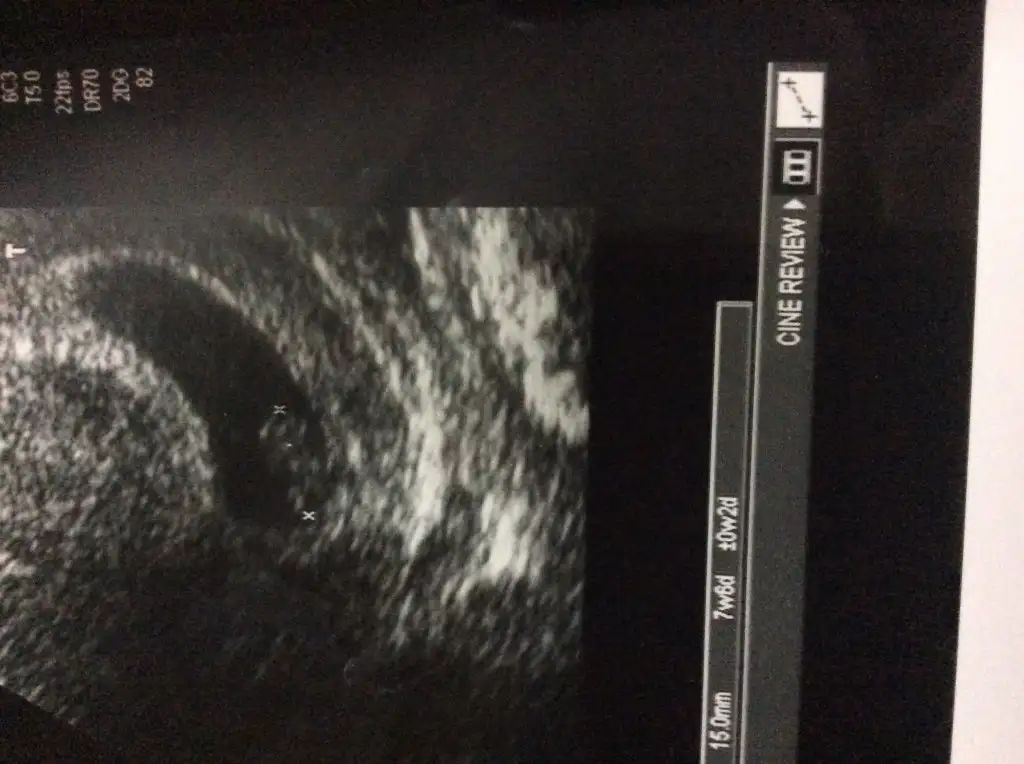

Gördüm gayettt sağlıklı, haftasıyla uyumluu, kalbi de pıt pıt atıyordu. Kusma ishale çevirince gaz sancıdı yapmış. Tüm sorun buymuş. Ama ben bebeğimi görmüş oldum :) fotosunu atıyorummm :)